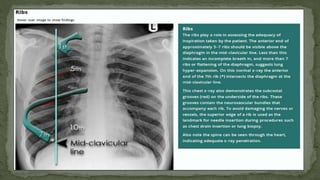

F. Inspiration (Degree of inspiration)

 To judge the degree of inspiration, count the number of ribs above the

diaphragm.

 The midpoint of the right hemi-diaphragm should be between the 5th and 7th

ribs anteriorly.

 The anterior end of the 6th rib should be above the diaphragm as should the

posterior end of the 10th rib.

 If more ribs are visible the patient is hyperinflated

 If fewer it indicates inadequate inspiration

 Poor inspiration will make the heart look larger, give appearance of basal

shadowing and cause the trachea to appear deviated to the right